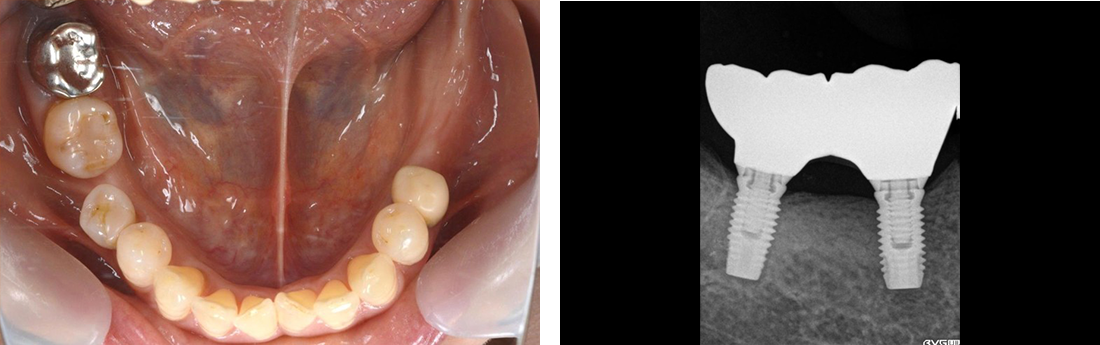

インプラント症例 Case2

Treatment cases

Before

After